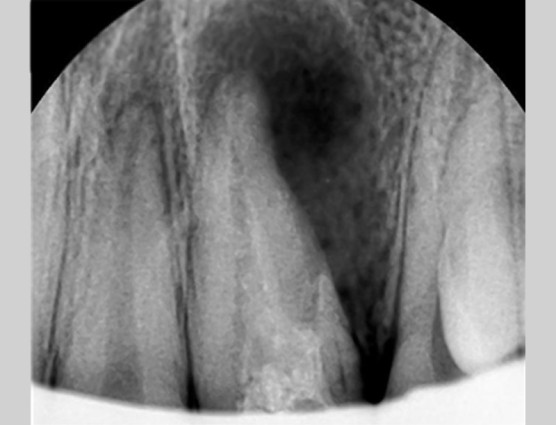

[신경관의 위치와 치아 천공의 위치]

하늘색의 신경관이 실제로 신경치료가 되어야하는 부분입니다.

하지만 파란색의 구멍을 막게 되면 좋아지리라 생각되었습니다.